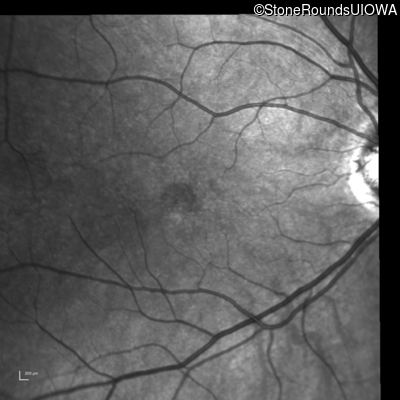

Infrared Fundus Photograph - Left - 20/40

Exemplar